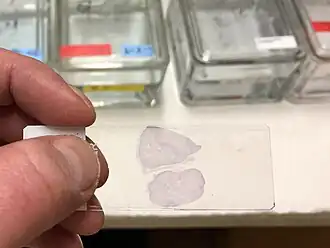

Mounting usually involves attaching the samples to a glass microscope slide for observation and analysis. In some cases, cells may be grown directly on a slide. For samples of loose cells (as with a blood smear or a pap smear) the sample can be directly applied to a slide. For larger pieces of tissue, thin sections (slices) are made using a microtome; these slices can then be mounted and inspected.

Papanicolaou

Papanicolaou staining, or PAP staining, was developed to replace fine needle aspiration cytology (FNAC) in hopes of decreasing staining times and cost without compromising quality. This stain is a frequently used method for examining cell samples from a variety of tissue types in various organs. PAP staining has endured several modifications in order to become a “suitable alternative” for FNAC. This transition stemmed from the appreciation of wet fixed smears by scientists preserving the structures of the nuclei opposed to the opaque appearance of air dried Romanowsky smears. This led to the creation of a hybrid stain of wet fixed and air dried known as the ultrafast papanicolaou stain. This modification includes the use of nasal saline to rehydrate cells to increase cell transparency and is paired with the use of alcoholic formalin to enhance colors of the nuclei. The papanicolaou stain is now used in place of cytological staining in all organ types due to its increase in morphological quality, decreased staining time, and decreased cost. It is frequently used to stain Pap smear specimens.[11] It uses a combination of haematoxylin, Orange G, eosin Y, Light Green SF yellowish, and sometimes Bismarck Brown Y.[10][11][12]